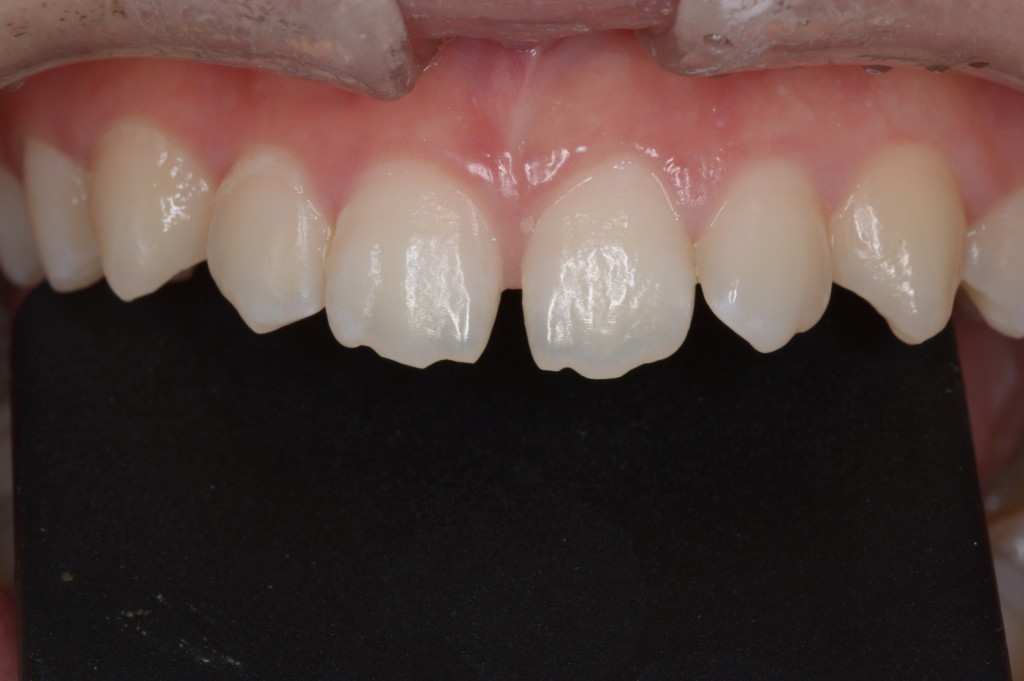

| 診断名・主な症状 | 重度叢生、狭窄歯列、前歯部交差咬合 |

左側【治療後】